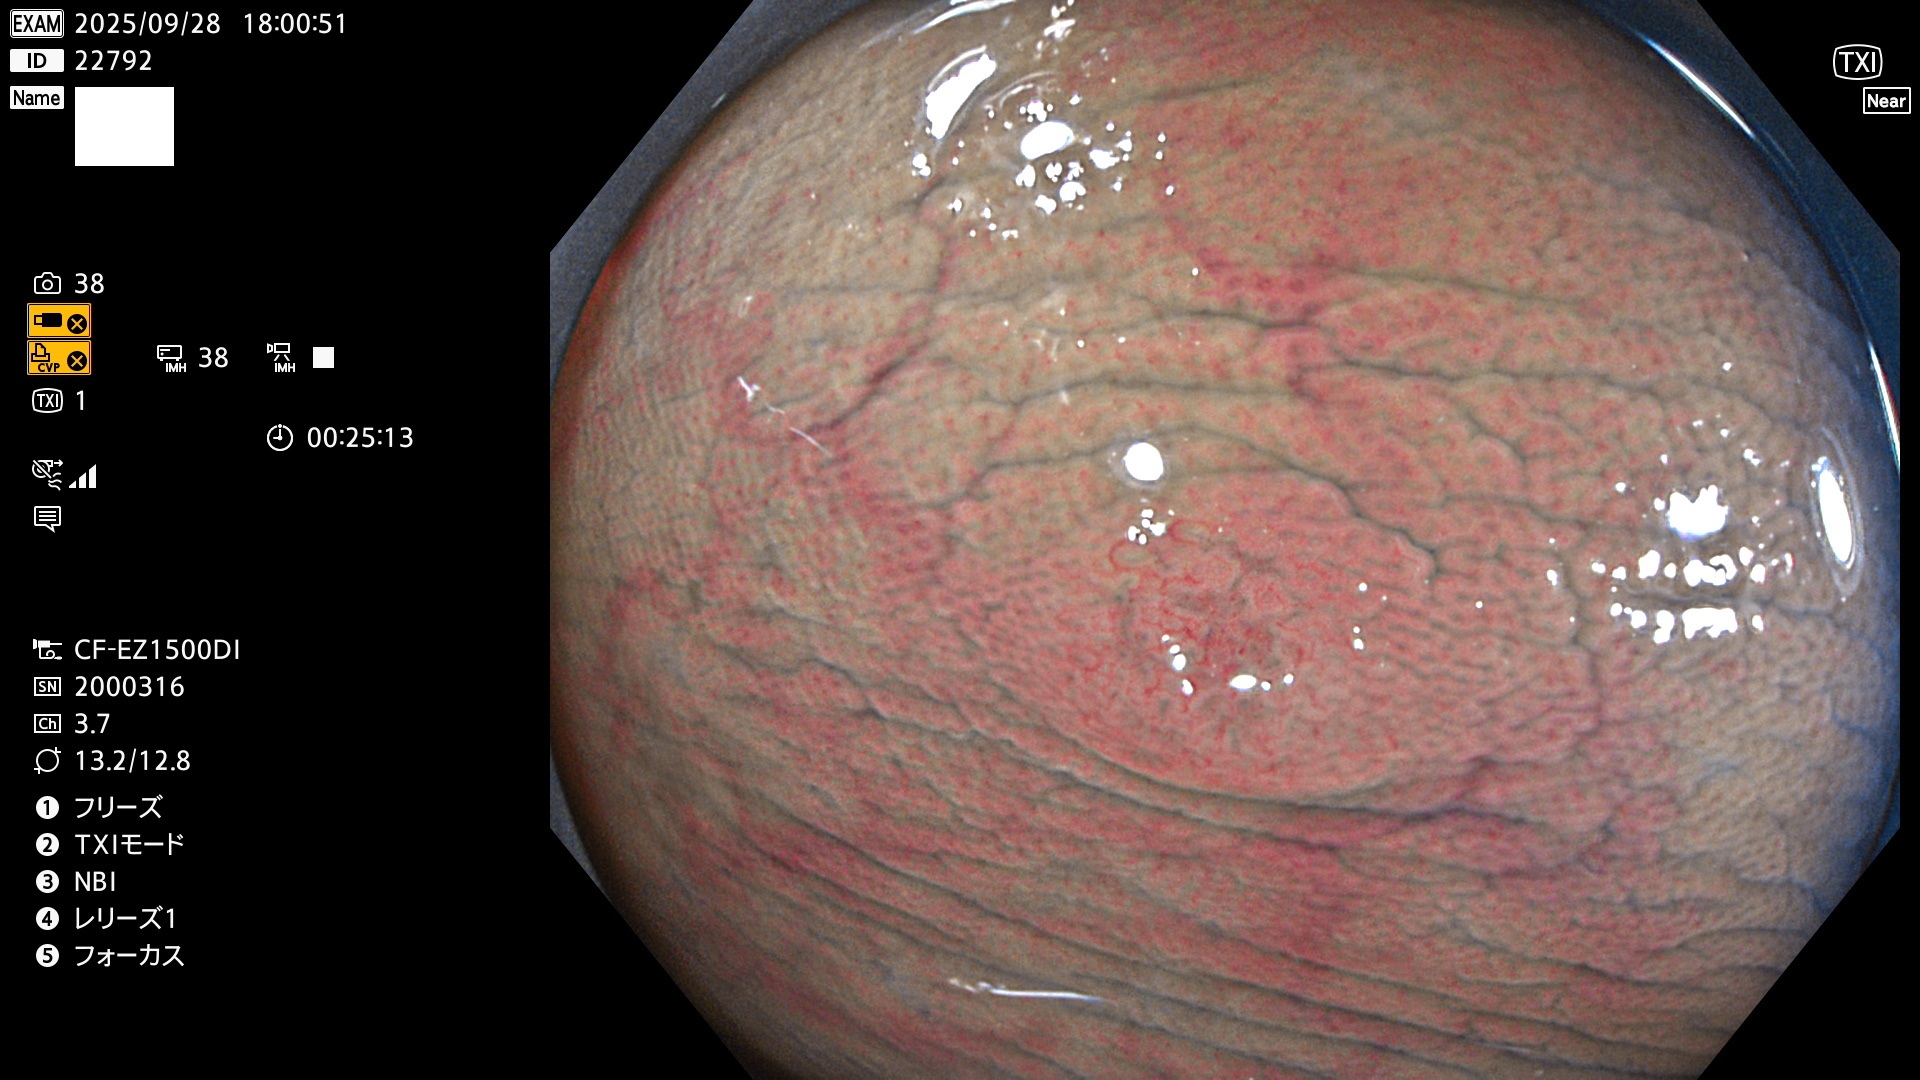

完全に平坦な物をUb、陥凹している物をUcと呼びます。Ubは認識が困難で、Ucはびらん(炎症)と紛らわしいために見落とされやすく、「内視鏡後・大腸癌」の原因になります。

専門的)Uc=De Novo癌? 内視鏡の解像度が低かった時代、このような説もありました。しかし今日の高精度内視鏡では良性の微小なUc型腺腫(APC遺伝子異常の腺腫)が日常的に見つかります。Ucこそが多段階発癌(Adenoma-Carcinoma Sequence)のMain Routeです。

毎週の検査(木・金・土・日)に発見されたUbとUc型・腺腫を、その週の日曜の夜にUPし1週間、提示します。

2025年9月25日〜9月28日の4日間(40件)4個 (Uc_ADR=4個/40人=10%)

2025年9月25日〜9月28日の4日間(40件)で4個 (Uc_ADR=4個/40人=10%)